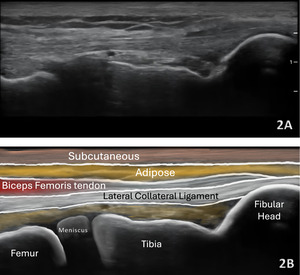

Lateral Meniscus

Figures 2A and 2B LAX View of Lateral Meniscus: The lateral meniscus demonstrates a triangular configuration but often appears slightly deeper and more curved than the medial meniscus. It lies beneath both the LCL and popliteus tendon, requiring careful angulation to eliminate anisotropy. Its increased mobility relative to the medial meniscus can be appreciated during subtle varus stress.